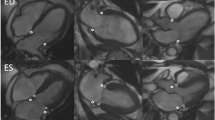

Right ventricular myocardial strain was measured blinded for randomization outcome in the 4 chamber longitudinal axis images using commercially available FT-CMR software (QStrain, Medis Medical Imaging Systems version 2.0.12.2, Leiden, The Netherlands) under the supervision of an experienced CMR cardiologist (JE, supervision AH). The right ventricular endocardial contours were drawn manually during the end-diastolic and end-systolic phase. Subsequently, the software automatically traced the cardiac contours during the cardiac cycle, resulting in the peak global longitudinal strain (GLS) of the entire right ventricle, GLS of the RV free wall (FWLS) and GLS of the septum. Since deformation of the intraventricular septum is considered to be mainly affected by LV dysfunction, we chose to focus on the total RV GLS and the RV FWLS, rather than GLS of the septum [18]. RV volumes were measured in the short axis images and corrected for body-surface area (AvV, supervision AH). For the calculation of the TAPSE, we measured the RV length in the 4 chamber longitudinal axis from the apex to the juncture of the tricuspid annulus with the RV free wall in end-diastole (end-diastolic length; EDL) and end-systole (end-systolic length; ESL), as described previously [19]. Then, the TAPSE was calculated by subtracting the ESL from the EDL. An example of the measurement techniques is displayed in Fig. 2.

Measurement of right ventricular function parameters. A and B End-diastolic length (A) and end-systolic length (B) measurement for the calculation of the tricuspid annular plane systolic excursion; C Right ventricular strain measurement using feature tracking, with the green line indicating tracking of the free wall and white line indicating the septum tracking; D Strain curves, with the upper curve indicating the general RV strain curve and the lower curve indicating the RV strain curves divided into septum (white), average (white) and free wall (green). eS indicates end-systolic and eD indicates end-diastolic; E, F Right ventricular contours in the short-axis end-diastole (E) and end-systole (F) for RV volume measurements